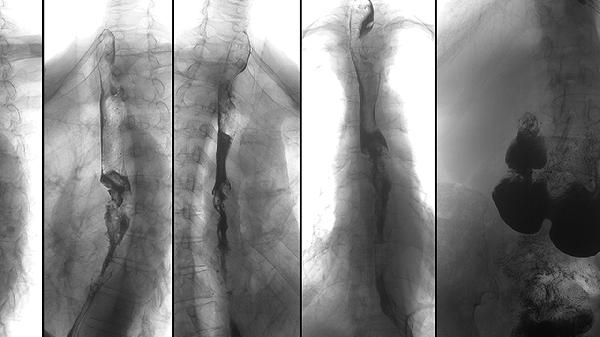

先天性成骨不全患者的骨骼生长速度较慢,容易出现畸形。治疗方法包括物理治疗,如水中运动,可以增强肌肉力量;佩戴支具,如脊柱矫形器,可以预防脊柱侧弯;手术治疗,如截骨术,可以纠正骨骼畸形。

先天性成骨不全患者骨骼脆弱,轻微外伤即可导致骨折。预防措施包括避免剧烈运动,选择低冲击力的活动,如游泳;居家环境安全,减少跌倒风险;使用护具,如护膝和护腕,保护易受伤部位。